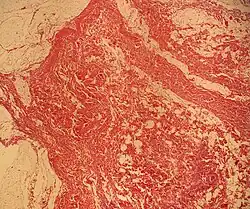

![Histopathology of a lipoma: The mass is composed of lobules of mature white adipose tissue divided by fibrous septa containing thin-walled capillary-sized vessels.[25][predatory publisher] H&E stain.](./_assets_/Histopathology_of_lipoma.jpg) Histopathology of a lipoma: The mass is composed of lobules of mature white adipose tissue divided by fibrous septa containing thin-walled capillary-sized vessels.[25] H&E stain.

Histopathology of a lipoma: The mass is composed of lobules of mature white adipose tissue divided by fibrous septa containing thin-walled capillary-sized vessels.[25] H&E stain. -

Histopathology of the major differential diagnosis of a well-differentiated liposarcoma, lipoma-like subtype: It looks almost identical at low magnification, but a high magnification of a fibrous band shows spindle cells with enlarged, hyperchromatic nuclei. H&E stain.

Histopathology of the major differential diagnosis of a well-differentiated liposarcoma, lipoma-like subtype: It looks almost identical at low magnification, but a high magnification of a fibrous band shows spindle cells with enlarged, hyperchromatic nuclei. H&E stain. -